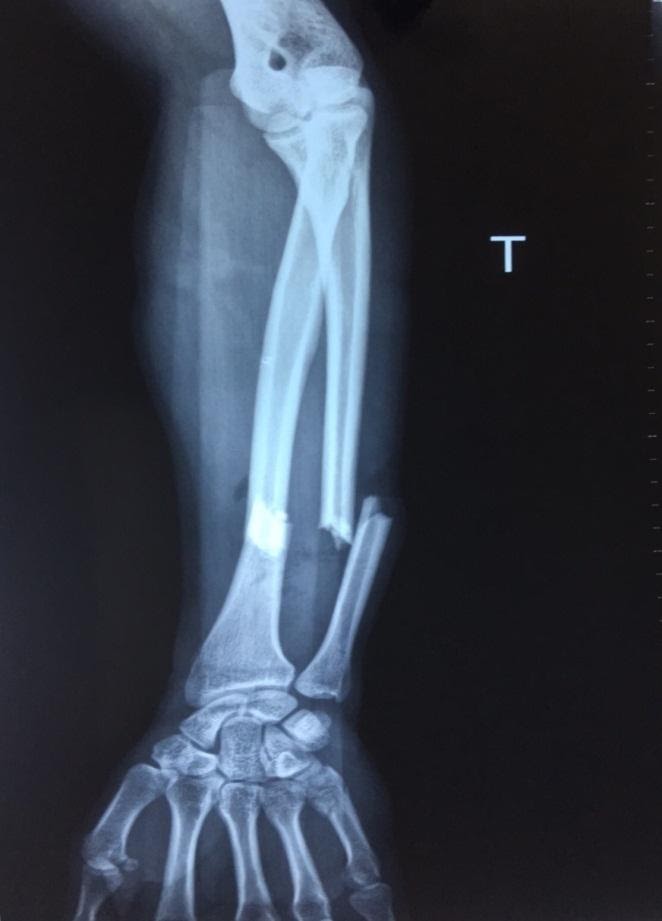

Ngày 21/4/2019, Khoa Ngoại, Trung tâm Y tế thành phố Móng Cái tiến hành phẫu thuật kết hợp gẫy hở 1/3 dưới 2 xương cẳng tay trái cho bệnh nhân C.V.T (21 tuổi), thường trú tại phường Trà Cổ, tp.Móng Cái, tỉnh Quảng Ninh. Bệnh nhân vào viện được chẩn đoán: Gẫy hở 1/3 dưới 2 xương cẳng tay trái, gẫy kín xương bàn ngón 5 tay trái, vỡ ổ chảo xương bả vai phải do tai nạn giao thông.

Khoảng 1h trước vào viện, Bệnh nhân bị tai nạn xe máy - ô tô, sau tai tạn tỉnh, không được sơ cấp cứu tại hiện trường. Vào viện trong tình trạng: Tỉnh, đau nhiều vùng vai phải, cẳng bàn tay trái. Cẳng tay trái 1/3 dưới sưng nề, biến dạng gập góc, vết thương có xương chồi ra kèm váng mỡ, mạch quay không bắt được. Mất vận động và cảm giác bàn ngón tay trái.

Kết quả X-quang, cắt lớp vi tính: Gẫy 1/3 dưới 2 xương cẳng tay trái di lệch, gẫy xơng bàn ngón 5 tay trái; Vỡ ổ chảo xương bả vai phải.

Trước phẫu thuậtSau phẫu thuật